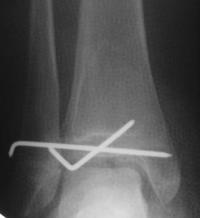

Fracture triplane

C’est une fracture survenant chez l’adolescent proche de la fin de la croissance.

C’est une fracture dans les 3 plans de l’espace qui associe le plus souvent un décollement épiphysaire Salter 2 et un décollement épiphysaire Salter 3 ou 4.

Un bilan par scanner peut aider à visualiser le trait de fracture et les déplacements.

Traitement : identique au traitement des fractures de type Salter 3 ou 4

- En cas d’absence de déplacement : immobilisation cruro-pédieuse 4 à 6 semaines

- En cas de déplacement (fracture articulaire) :

- réduction anatomique sous anesthésie générale

- ostéosynthèse par broches ou vis et immobilisation par botte plâtrée 6 semaines

- Reprise de l’appui partiel au déplâtrage avec augmentation progressive de l’appui pour un appui complet à 3 mois

- Ablation du matériel vers le 3ème mois pour les broches. En cas d’ostéosynthèse par vis l’ablation du matériel peut être réalisée plus tardivement jusqu’à 6 mois ou 1 an post opératoire

- Reprise des activités sportives à 4 mois